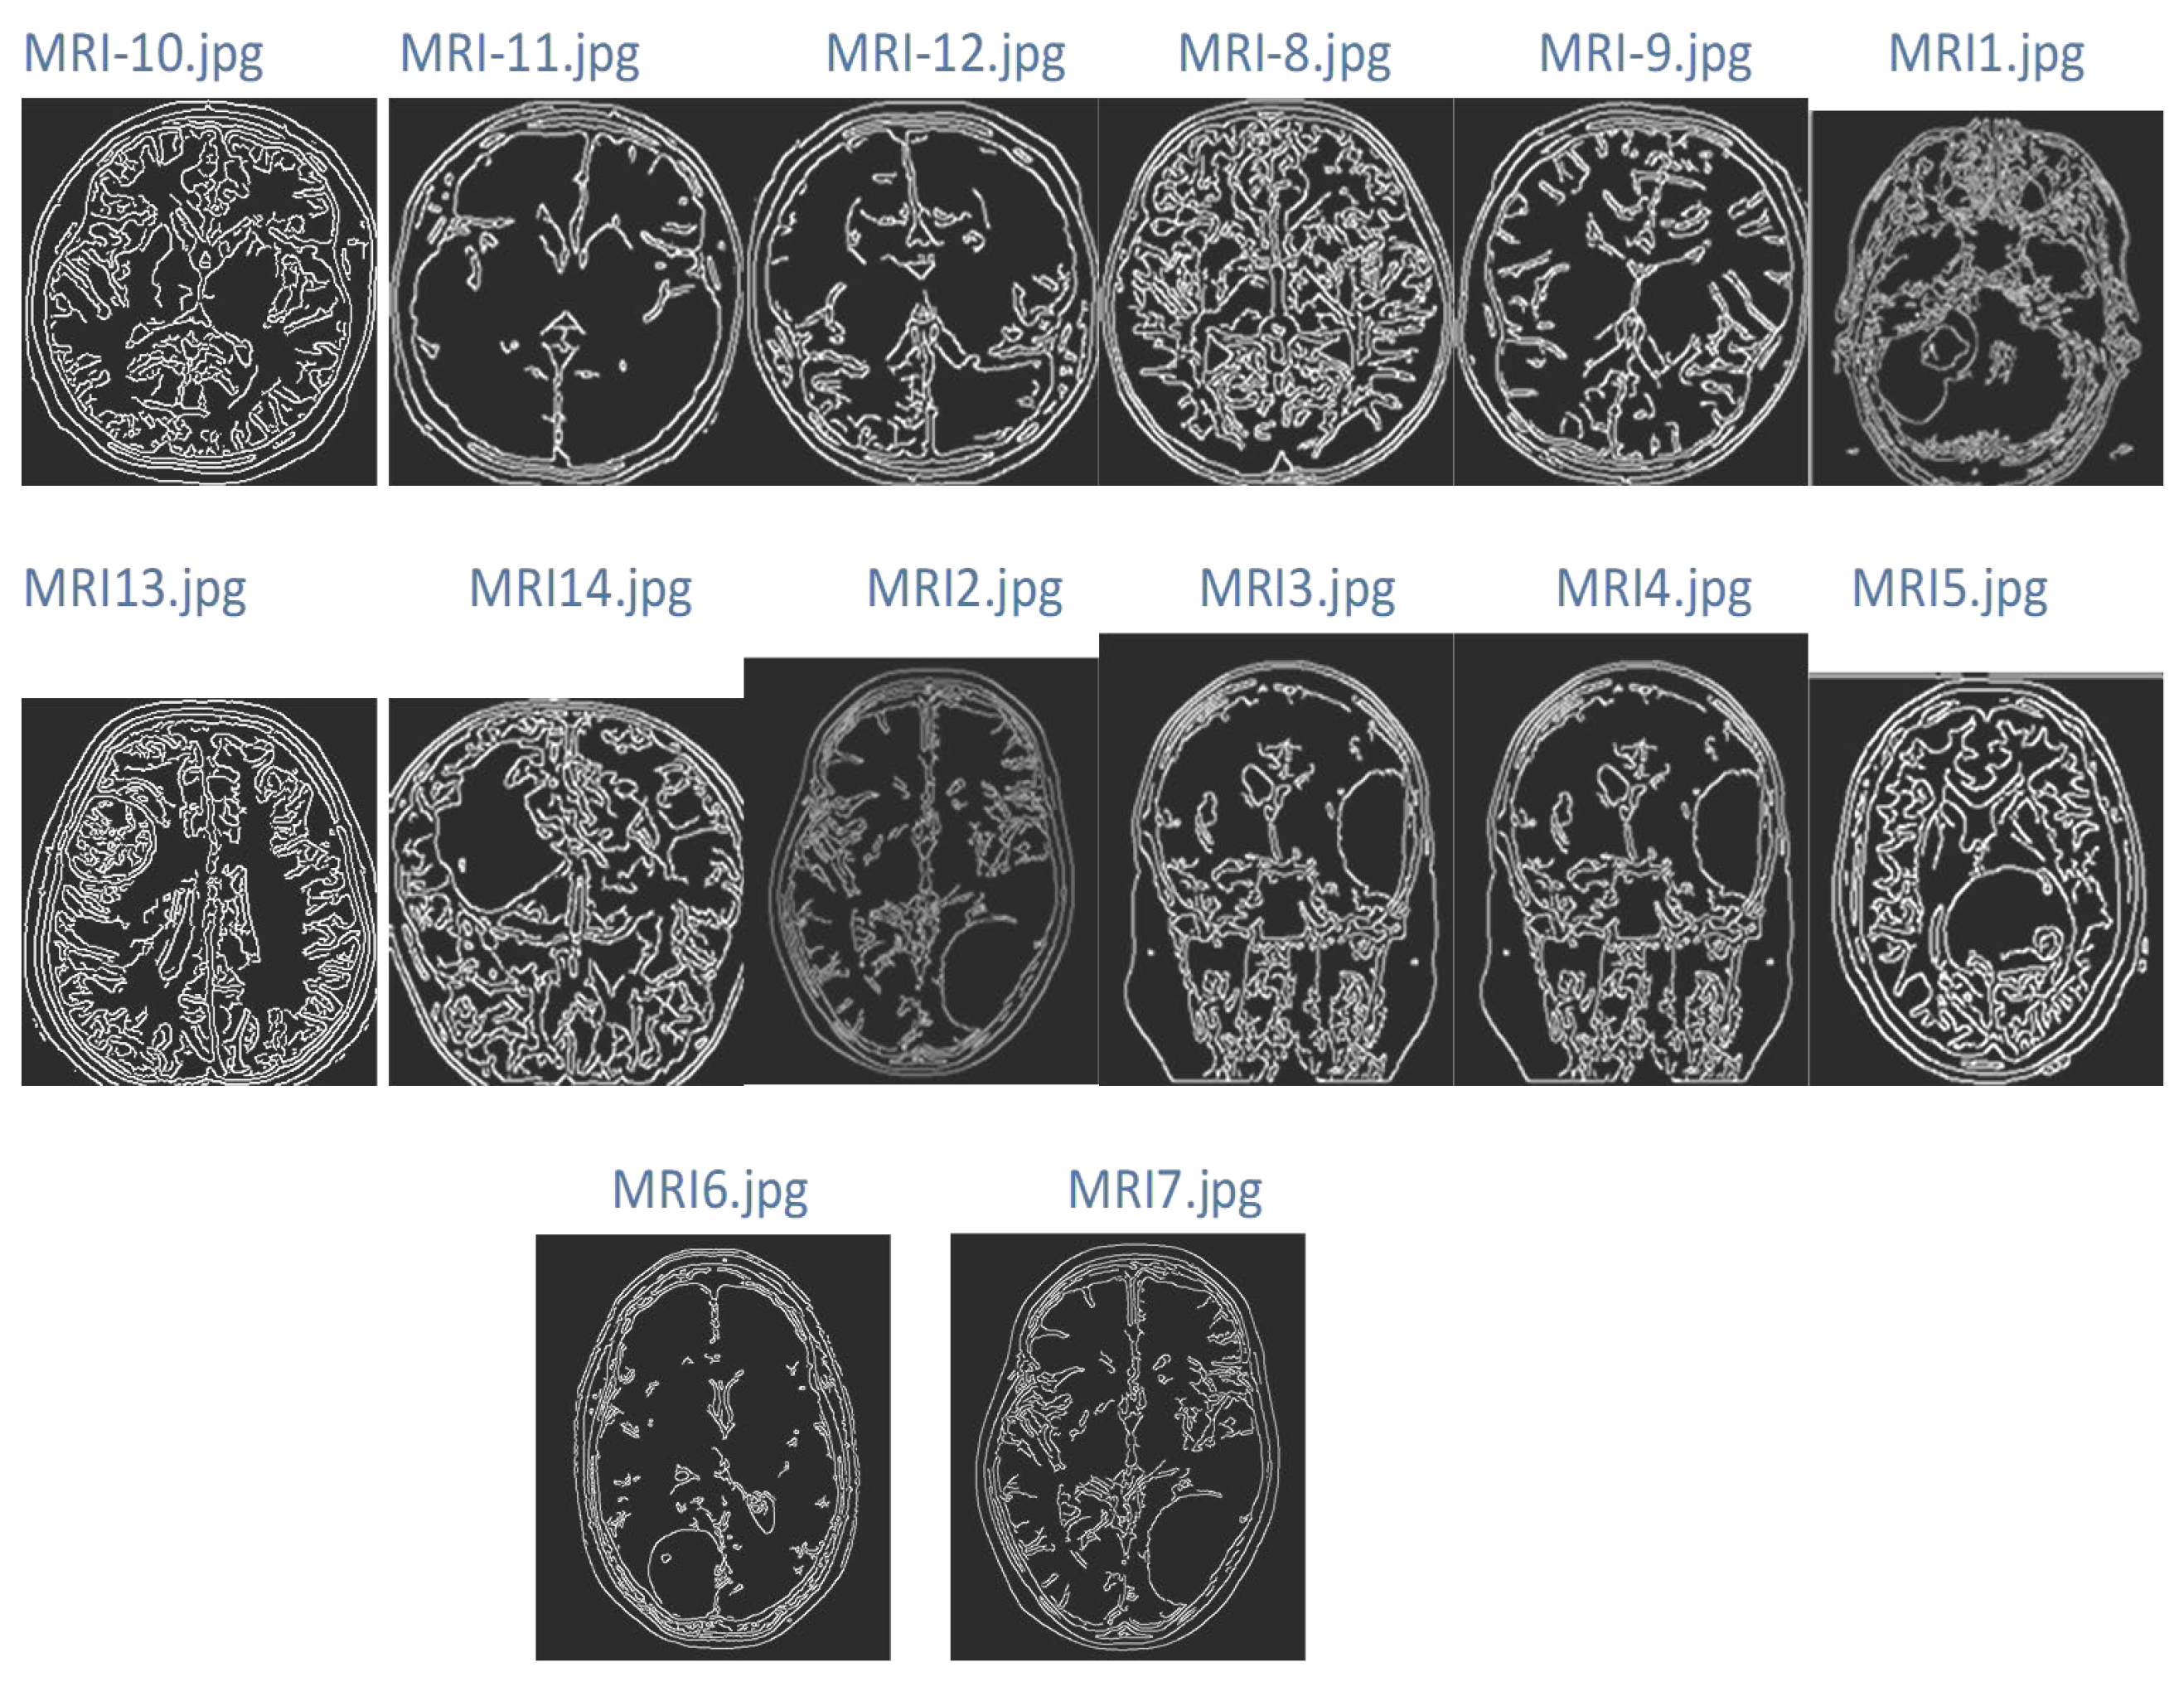

| Test MRI Image Sample | Improved MRI Samples | Feature of MRI Samples | Classification Result | |

|---|---|---|---|---|

| Cluster 1 (Normal) | Cluster 2 (Tumor) | |||

![]() | ![]() | ![]() | ![]() | |